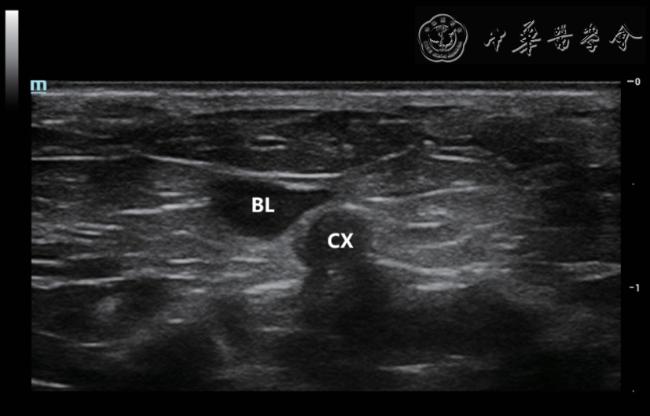

2. 研究方法:将3%戊巴比妥钠注射液(剂量50 mg/kg)注射入孕鼠腹部,使其深度麻醉后放置于操作台上。用剃毛器剃净孕鼠腹部绒毛,涂少量耦合剂并放置超声凝胶贴片。调整超声探头的角度及深度,在下腹部横切面显示宫颈(图1),转动探头分别调整至孕鼠双侧子宫体长轴方向,可见多个妊娠囊在双侧子宫体内依次呈串珠样相邻排列(图2),分为膨大部及缩细部:膨大部内见妊娠囊、胎鼠、胎盘、羊水;膨大部之间为环状缩细部(图3)。打开彩色多普勒成像,调整速度标尺约4.5 cm/s,增益设置约为50 dB,扫查孕鼠子宫胎盘循环:孕鼠UtA 起自髂内动脉的分支膀胱上动脉,自宫体宫颈交界处转向头侧,于子宫内侧缘沿宫体轮廓弯曲走行(图4a、4b),沿途发出数个子宫动脉分支(uterine artery branches,UtB)向胎盘内延伸(图4c);卵巢动脉(ovarian artery,OA)在肾动脉稍下方自腹主动脉发出,分为输卵管支、卵巢支及子宫支(图4d)。在自宫颈向上的第一、第二、第三和第四妊娠囊旁测量UtA 多普勒频谱,命名为UtA-1、UtA-2、UtA-3 和UtA-4,于第四妊娠囊旁测量UtB 多普勒频谱(图3);于OA 中段测量OA 频谱。测量部位选取上述血管走行较平直段,超声入射角度尽可能接近0°不得超过45°,取样门大小保持在0.3 ~ 0.5 mm 之间。至少获得3个及以上完整清晰的频谱时,固定图像,测量收缩期峰值流速(peak systolic velocity,PSV)、舒张末期流速(end diastolic velocity,EDV)、收缩期峰值流速与舒张末期流速比值(PSV/EDV,S/D)、阻力指数(resistance index,RI)、搏动指数(pulse index,PI)(图5)。每个部位分别测量2 次并取平均值。

图1 孕鼠宫颈灰阶超声图像

注:BL 为膀胱,CX 为宫颈